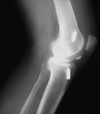

what is this finding called? association?

A

Segund fx

bony aculsion of anterolateral ligament

pathognominic for acl tear

associated with acl tear 75-100 percent of the time.